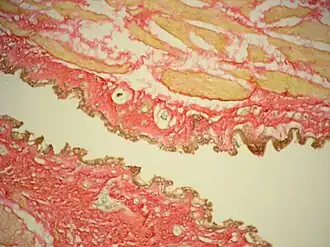

Окраска по Ван Гизону

Окраска по Ван-Гизону — метод окраски микропрепаратов в гистологии, предназначенный для изучения структуры соединительной ткани. Красителем служит смесь кислого фуксина и пикриновой кислоты, причем первый компонент окрашивает коллагеновые волокна в ярко-красный цвет, а второй придает прочим структурам ткани жёлтую окраску. Окраска разработана американским психоневрологом и патологом Айрой Ван-Гизоном в 1889 году.

В результате окраски ядра клеток приобретают чёрный цвет, коллаген – красный, другие тканевые элементы (включая мышечные волокна и эритроциты) – жёлтые, фибрин – жёлтый или оранжевый.